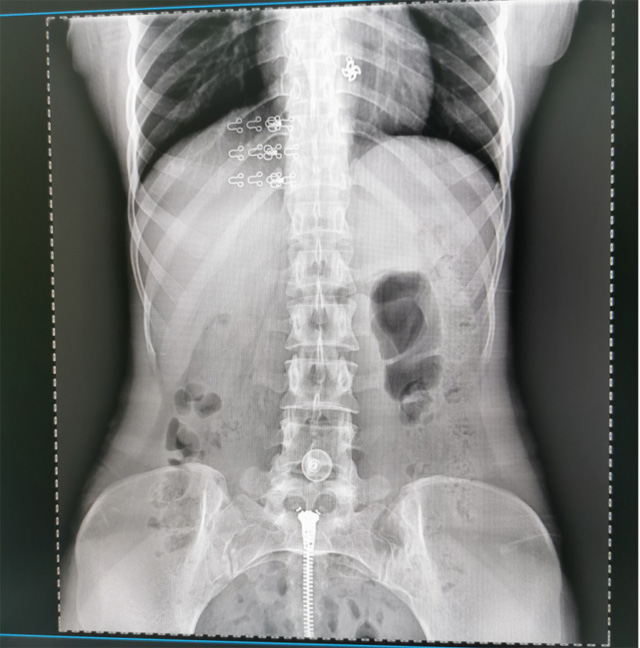

懸吊DR數(shù)字化攝影圖像質(zhì)量高輻射量少誤差小滿足疾病的臨床診斷

提高醫(yī)院的影像科的醫(yī)療服務(wù)水平,滿足滿足人民群眾不斷增長的醫(yī)療需求,促進醫(yī)療技術(shù)快速發(fā)展。醫(yī)院都引進懸吊DR拍片設(shè)備新一代數(shù)字化X線攝影系統(tǒng)。標志著醫(yī)院的診療水平又上升一個新的臺階。懸吊DR滿足人體頭部、胸部、腹部、腰椎、四肢等部位的數(shù)字攝影檢查,可以檢查呼吸系統(tǒng)疾病,心臟系統(tǒng)的疾病、骨關(guān)節(jié)系統(tǒng)的疾病,子宮輸卵管造影、胃腸道造影,.有職業(yè)病體檢篩查塵肺病功能。通過DR數(shù)字化攝影,分段連續(xù)、重疊采集數(shù)字化圖像,利用軟件對圖像進行拼接的方式來獲得全脊柱、全上肢或全下肢的圖像。新設(shè)備的圖像更清晰,臨床拍攝避免患者再次搬運和移動產(chǎn)生的痛苦,是創(chuàng)傷骨折患者的福音。輻射減少受照劑量50%,后處理能力強、圖像質(zhì)量高。有效降低操作難度,縮短工作流程,尤其適合大批量體檢。

具有射線劑量小、圖像清晰度高、誤差小等特點,懸吊DR已廣泛應(yīng)用于各級醫(yī)療機構(gòu)的體檢中心,越來越受到臨床醫(yī)生的肯定和患者的青睞。為臨床診斷工作提供更加直觀有效的技術(shù)支持,大大提高了患者就醫(yī)效率從而為患者提供更加優(yōu)質(zhì)的醫(yī)療服務(wù)。提高了其成像質(zhì)量和臨床應(yīng)用價值,并極大減少了受照輻射劑量。有效滿足了各種常見疾病的臨床診斷和治療需求。以醫(yī)療質(zhì)量為根本,以優(yōu)質(zhì)服務(wù)為導(dǎo)向,竭誠為人民群眾的健康保駕護航。